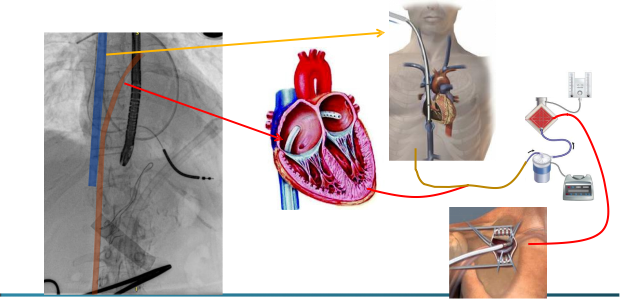

正性肌力药物的指南推荐:

I级推荐仅用于心源性休克的患者;

IIa类推荐用于心脏移植的桥接治疗;